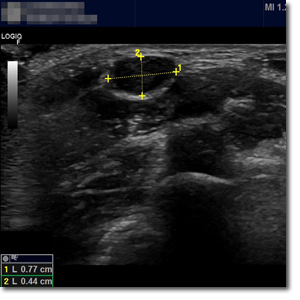

¿Qué es e­sa tu­mo­ra­ción en el cue­llo? U­se­mos la e­co­gra­fía pa­ra sa­ber­lo

Niño de 7 años que acude a consulta de Atención Primaria por aparición de tumoración cervical de 2 días de evolución. A la exploración en la región lateral cervical posterior al esternocleidomastoideo se aprecia una tumoración móvil no adherida de consistencia blanda de aproximadamente 1 cm de diámetro sin cambios superficiales acompañantes.